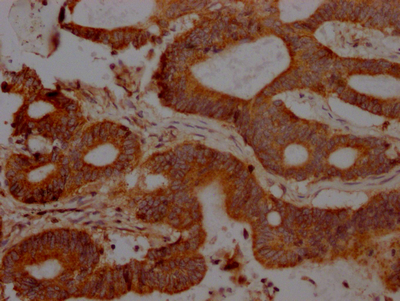

ApplicationELISA, WB, IHC; Recommended dilution: WB:1:500-1:5000, IHC:1:50-1:200